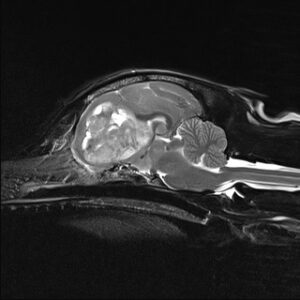

Under the care of Senior Surgeon Guillaume Leblond, Branson had an MRI scan of his brain which identified a mass on the left side of his brain, consistent with a meningioma or other extra-axial tumours. An extra-axial tumour is one that is growing outside of the brain tissue under the skull. He then had a CT scan which helped Guillaume to plan Branson’s brain surgery.